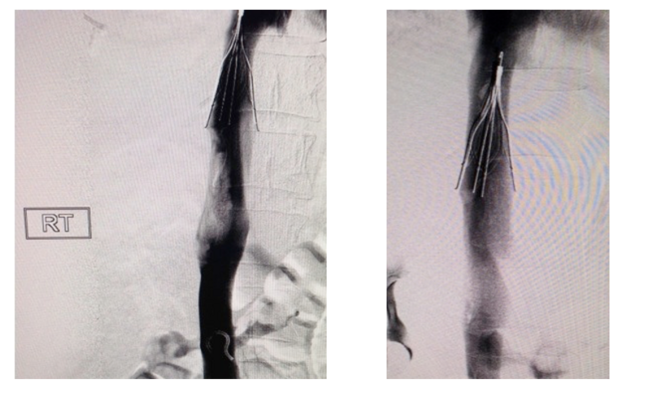

SALT LAKE CITY, UT — VentiV Scientific announced the FDA clearance of VentiV Mechanical Thrombectomy system to remove blood clots from the peripheral vasculature including the new VentiV Pulse platform.

During most thrombectomy procedures, clinicians access the femoral artery or vein; track a catheter over a guidewire to the thrombi (blood clot) or emboli; and then apply suction with a syringe, aspirator, and/or electromechanical pump. Blood clot age, size, and location plus catheter size, type, shape, and aspiration force a

re important variables during thrombectomy. Electric pumps can aspirate fast, but are often associated with significant blood-loss.